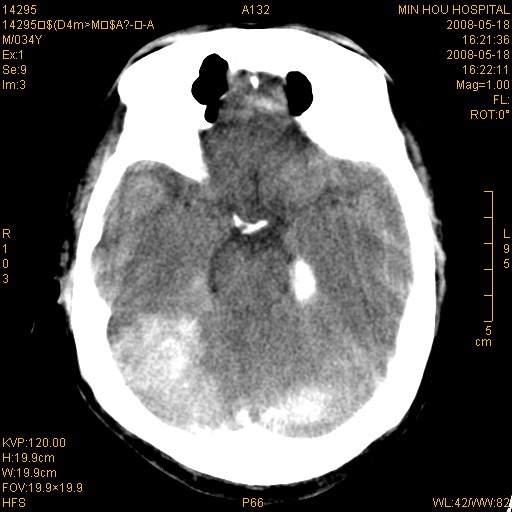

标题: CT13617:双顶叶白质水肿伴大脑镰小脑幕广泛钙化 [打印本页]

多年前频发抽搐生活不能自理,行ct平扫,诊断为双顶叶占位。因贫未能进一步检查。

目前偶有抽搐,能从事油漆工作。原片未能获取。

双侧侧脑室后脚旁对称性低密度影,符合肾上腺白质营养不良(成人型)改变    小脑幕及大脑廉钙化  可考虑为生理性

支持:1、肾上腺白质营养不良.2、小脑幕、大脑镰广泛钙化。3、建议进一步检查。

硬脑膜钙化是主因,双侧顶叶白质密度减低是可能由于静脉路回流受阻所致。

不排除脑静脉窦血栓形成;建议行进一步检查。